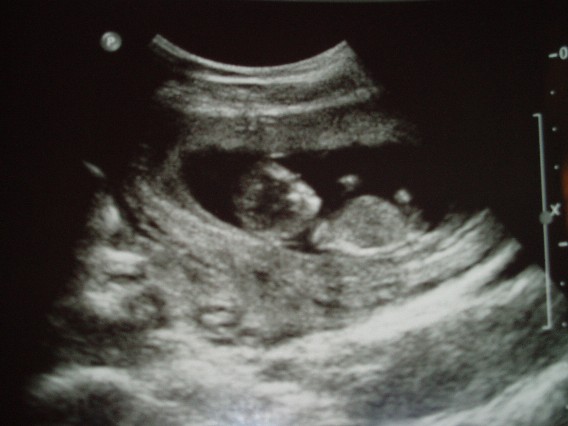

A Baba:

Kép

B Baba:

Együtt:

Kép[/quote]